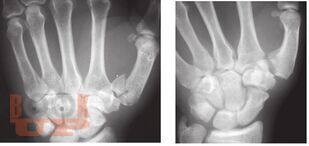

В пособии рассматриваются различные заболевания и травмы конечностей в аспекте их выявления лучевыми методами. Пособие составлено с учетом комплексного подхода к патологиям (костей и мягких тканей, суставов, сосудов, нервов) и диагностических методов (классического рентгеновского, КТ, МРТ, ультразвукового).